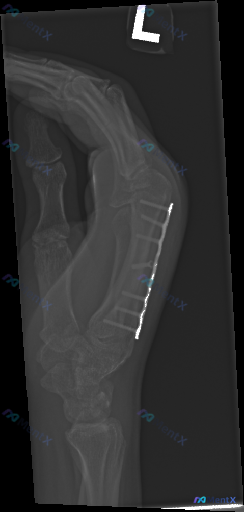

整理了一份左手第3掌骨术后的侧位X光片资料,先看一下影像描述: - 第3掌骨掌侧可见钢板及多枚螺钉内固定 - 骨折线已不明显,解剖序列基本正常 - 未见明显急性脱位、异常肿胀或异物 - 报告最终考虑为“术后内固定状态” 但仔细想一下,这张侧位片真的能完全排除“不正常”吗? 大家觉得这份影像里,最容易...